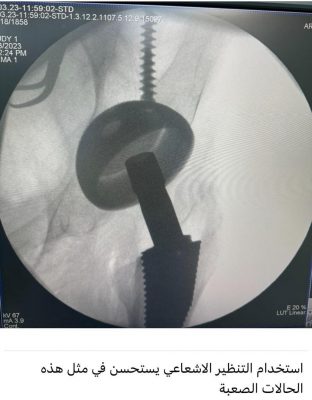

مضيفاً : وصلت المريضة للمستشفى وتم إجراء كافة التحاليل والفحوصات والإشاعات المطلوبة و التي أكدت إمكانية إجراء عملية تغيير مفصل كامل للورك بأمان رغم صعوبة التغيرات العظمية للورك وضمور العضلات وقصر الرجل وتمت العملية بنجاح ولله الحمد لتضاف للجراحات النوعية في جراحة استبدال مفصل الورك التي تتم في المستشفى ،وتؤكد على تطور الخبرات الطبية بالمستشفى بأحدث التقنيات الطبية الحديثة المتطورة عالمياً.